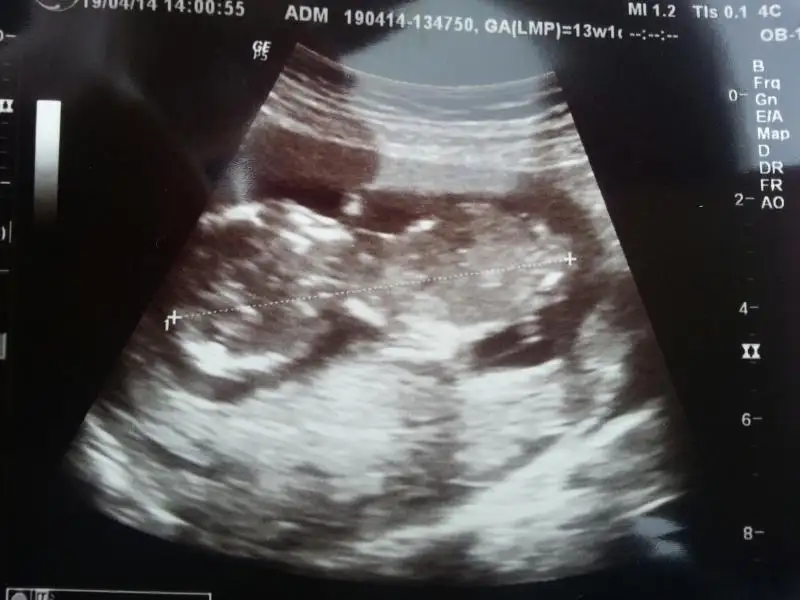

dr soylemeden siz gorun genital nub teorisi ( bebegin cinsiyeti)

Canım ben yanıldım galiba arkası dönükmüş tahminimi geri aldım kemik yapısı erkek gibi Allah gönüllerimizdekini nasip etsin